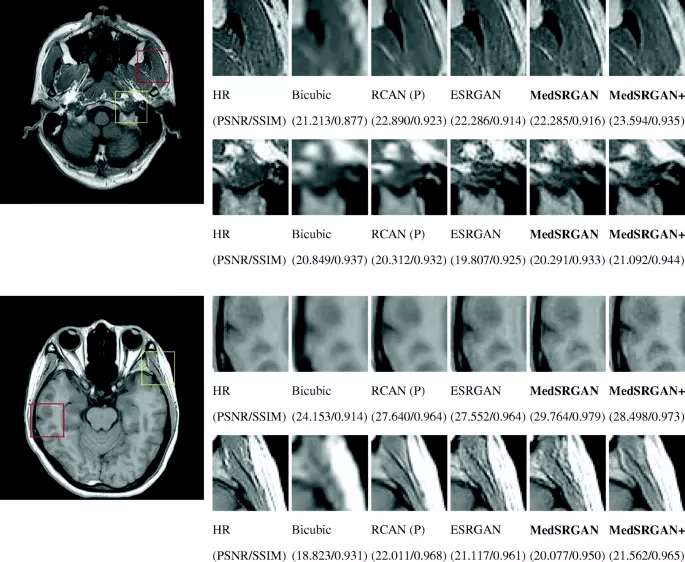

The possibility of image improvement allows us to implement GANs in medicine for Photo-Realistic Single Image Super-Resolution. Why is this significant?

The reason for the high demand for GANs in healthcare is that images should fit particular requirements and be high-quality. High image quality can be difficult to obtain under certain measurement protocols; for example, there is a strong need to decrease the effect of radiation on patients when using low-dose scanning in Computer Tomography (CT, to reduce the harmful effect on people with certain health pre-conditions such as lung cancer) or MRI. It has the effect of complicating efforts to obtain good quality pictures because of the poor quality scans.

Super-resolution improves the captured images and can remove the noise quite well, however adoption of GANs in the medical area is quite slow as many experiments and trials have to be made due to safety concerns. When dealing with healthcare, it is mandatory to involve a number of domain experts to evaluate the models and ensure the denoising does not distort the actual content of the image in some way that could lead to an incorrect diagnosis.